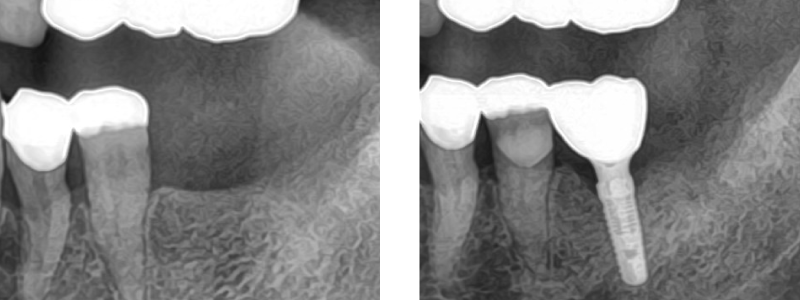

インプラント症例

治療内容 60代男性 割れていた歯を抜歯しインプラント埋入

期間 約2ヵ月

費用 385,000円

(インプラント275,000円+骨再生100,000円)

注意点/副作用 外科処置が必要・全身状態によりできない場合がある。